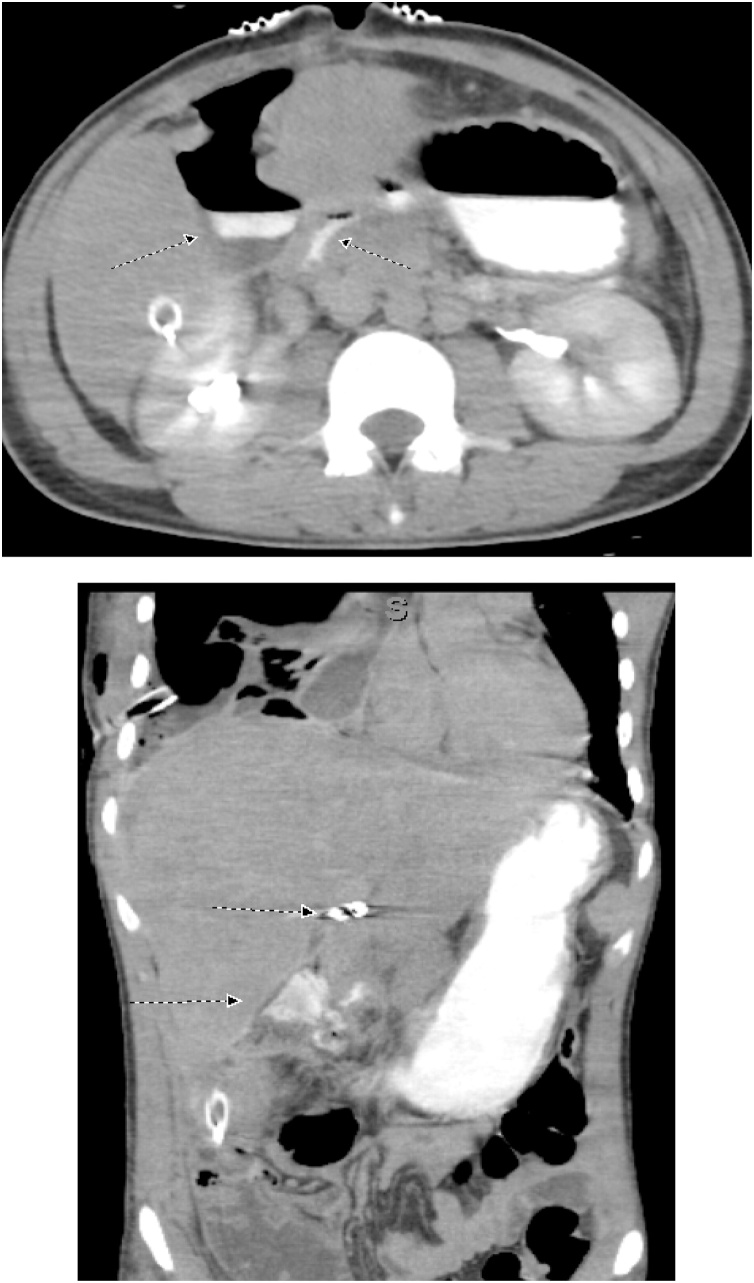

On the tenth postoperative day, the patient complained of a sudden severe abdominal pain. He was pale. The blood pressure was 88/48 mm Hg and pulse rate 142 per minute. The abdomen was tender. CT was done after resuscitation, showed a 24 cm × 13 cm × 8.2 cm heterogeneous subcapsular hepatic hematoma and a 1-cm IHPA (Fig. 9). Superselective hepatic angiography showed an IHPA of the right hepatic artery. The entry and exit points of the aneurysm were successfully embolized with two microcoils (Fig. 10). The patient was discharged home a few days later. No complications were reported during one year of follow up.

Fig. 9.

CECT abdomen showed the IHPA, marked by dotted circle along with subcapsular hematoma.